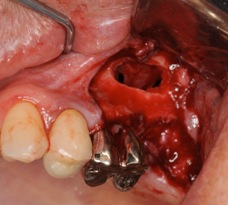

術前のCT画像、このように骨の厚みがほとんどありません

サイナスリフトをしている様子、横から骨を取り、上顎洞の粘膜を剥離していきます

粘膜が薄かったことが原因で粘膜が破れてしまい、サイナスリフトは中止、ここで

無理をしてオペをしてもいいことはないので、中止の勇断も必要です